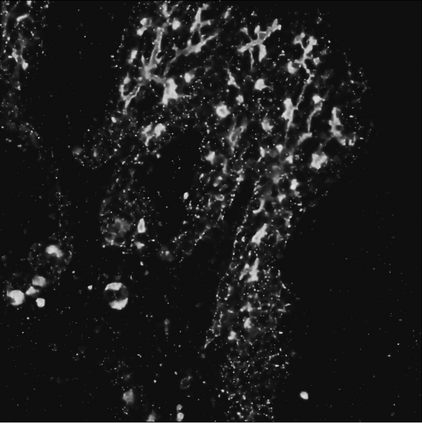

Motivated by the challenging segmentation task of pancreatic tubular networks, this paper tackles two commonly encountered problems in biomedical imaging: Topological consistency of the segmentation, and expensive or difficult annotation. Our contributions are the following: a) We propose a topological score which measures both topological and geometric consistency between the predicted and ground truth segmentations, applied to model selection and validation. b) We provide a full deep-learning methodology for this difficult noisy task on time-series image data. In our method, we first use a semisupervised U-net architecture, applicable to generic segmentation tasks, which jointly trains an autoencoder and a segmentation network. We then use tracking of loops over time to further improve the predicted topology. This semi-supervised approach allows us to utilize unannotated data to learn feature representations that generalize to test data with high variability, in spite of our annotated training data having very limited variation. Our contributions are validated on a challenging segmentation task, locating tubular structures in the fetal pancreas from noisy live imaging confocal microscopy. We show that our semi-supervised model outperforms not only fully supervised and pre-trained models but also an approach which takes topological consistency into account during training. Further, our approach achieves a mean loop score of 0.808 for detecting loops in the fetal pancreas, compared to a U-net trained with clDice with mean loop score 0.762.